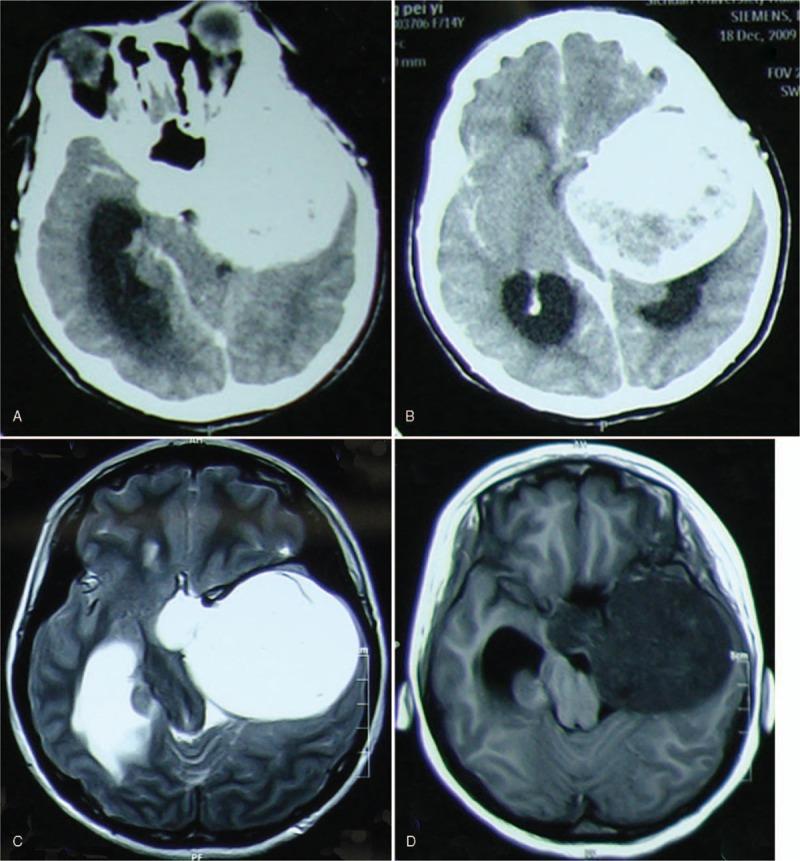

MRI revealed a lesion that extends to the greater wing of the sphenoid bone as well as the pituitary fossa. Our initial diagnosis was a sphenoid wing meningioma but interestingly, histopathology revealed solid cavernous hemangioma.

磁共振成像(MRI)显示一个病变延伸至蝶骨大翼以及垂体窝。我们最初的诊断是蝶骨嵴脑膜瘤,但有趣的是,组织病理学显示为实性海绵状血管瘤。